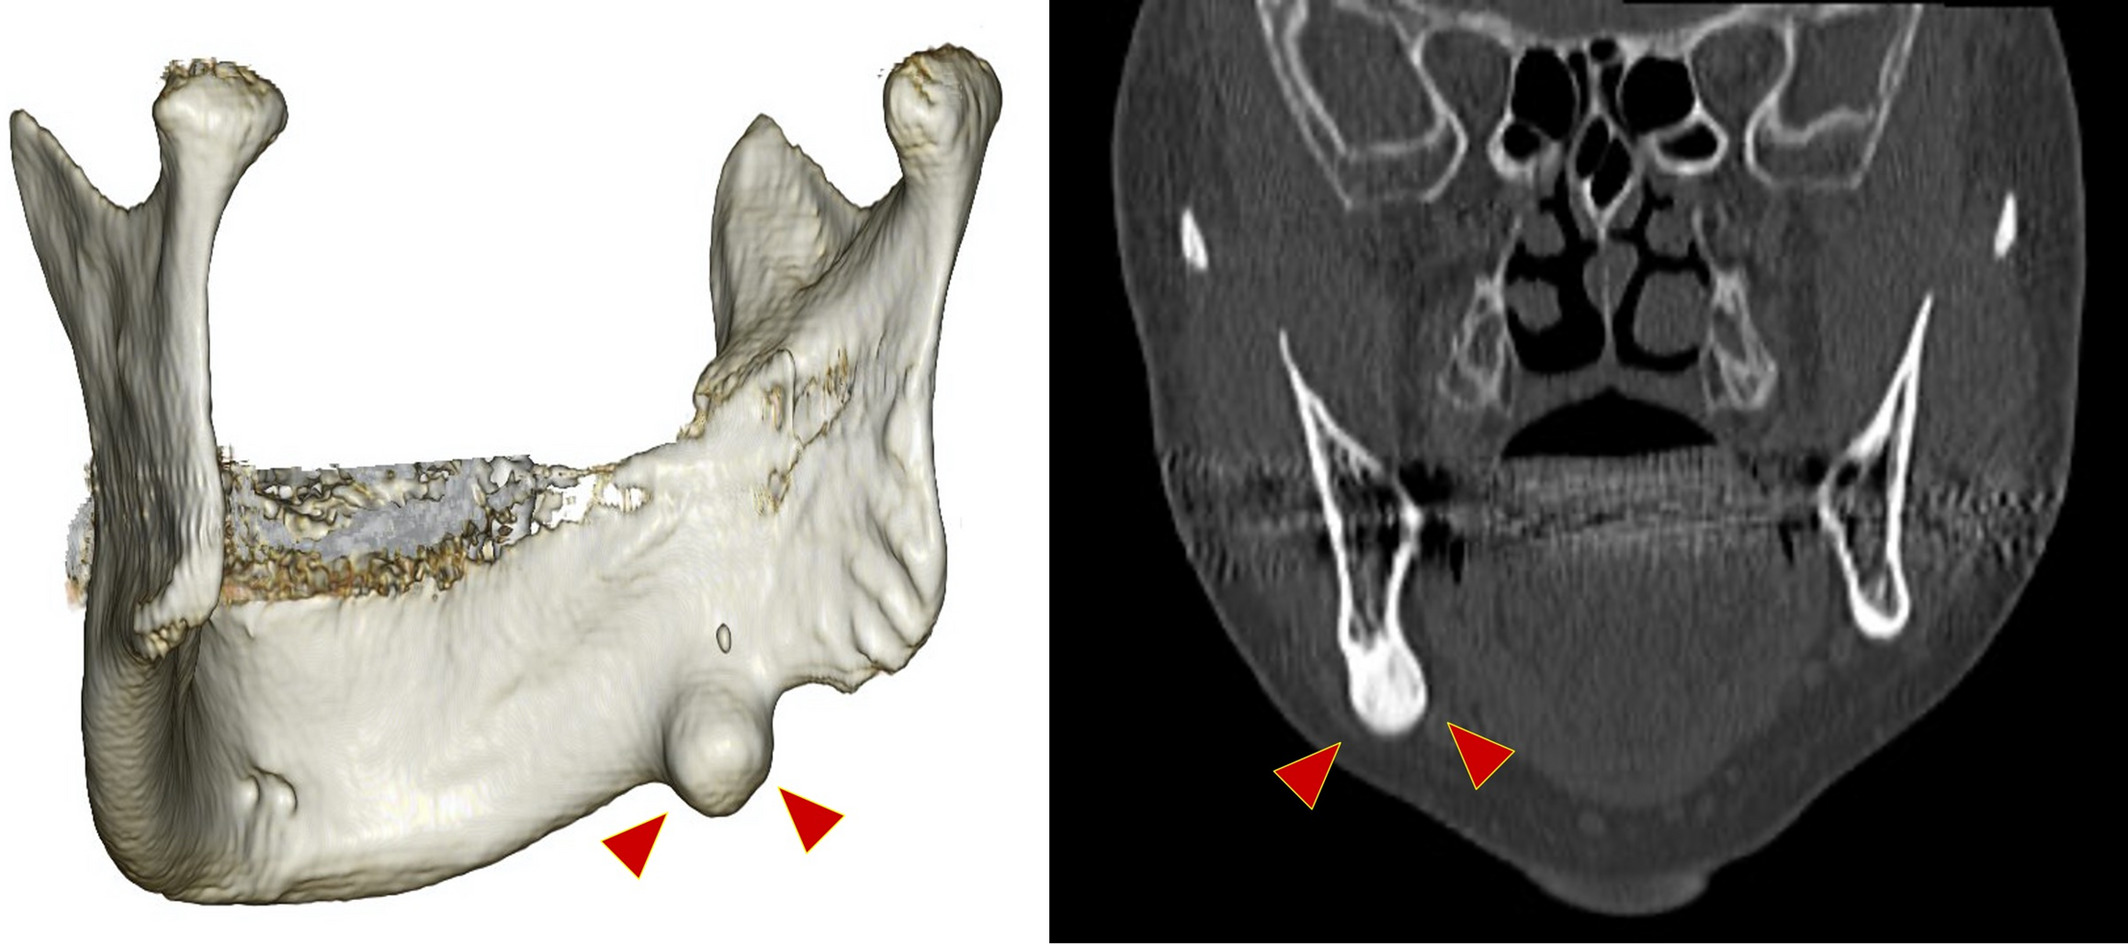

Osteoblastoma

3d printerleriň medisinada ulanylyşy